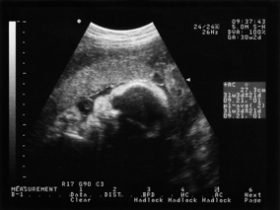

Il suo viso è cambiato. I capelli, le ciglia e le sopracciglia crescono e si può individuare il colore dei suoi capelli. Gli occhi rimangono ancora chiusi, anche se reagiscono alla luce viva.